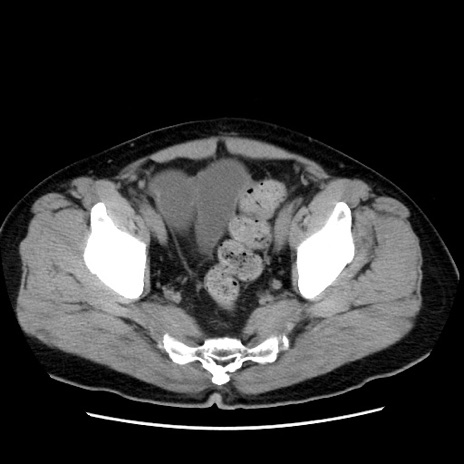

症例16(横断像)

【症例】 70歳代男性

【主訴】 腹痛、嘔吐

【現病歴】 約1ヶ月前より間欠的に腹痛と嘔吐あり、当院消化器内科を受診したところCTで多発する肝臓のLDAを指摘され、精査中であった。以降は消化器症状は安定していたが、2日前より嘔気と腹痛があり、同日より排便・排ガスが消失した。改善認めず、 本日、救急外来を受診した。

【既往歴】 大腸ポリープ切除後。

【身体所見】意識清明・会話良好、BT 36.3℃、BP 127/80mmHg、 P 80bpm、腹部:膨満あり、平坦・軟、上腹部正中および下腹部正中に圧痛あり、反跳痛なし、筋性防御なし。

【データ】WBC 7200、CRP 0.77